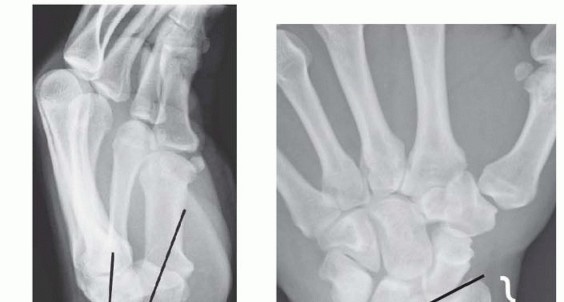

IMAGING AND OTHER DIAGNOSTIC STUDIES

TECH FIG 3 • A,B. PA and lateral views demonstrating reduction of distal radius fracture. C. The incision is made over the radial styloid.(continued)

TECH FIG 3 •(continued)D. A pin is inserted retrograde into the radial styloid. E. PA radiograph demonstrating the course of the radial styloid wire. F. Two radial styloid wires and two dorsoulnar wires are in place. G. PA view showing fixation and the path of the wires. H. Lateral view showing fixation and path of wires. I. Pins are bent, cut, and covered above the skin. The pins are cut just beneath the skin, which is closed with a 5-0 nylon suture. Alternatively, the pins are bent and cut and left outside the skin ( TECH FIG 3I). A dressing and splint are then applied.3. Bridging External Fixator Application